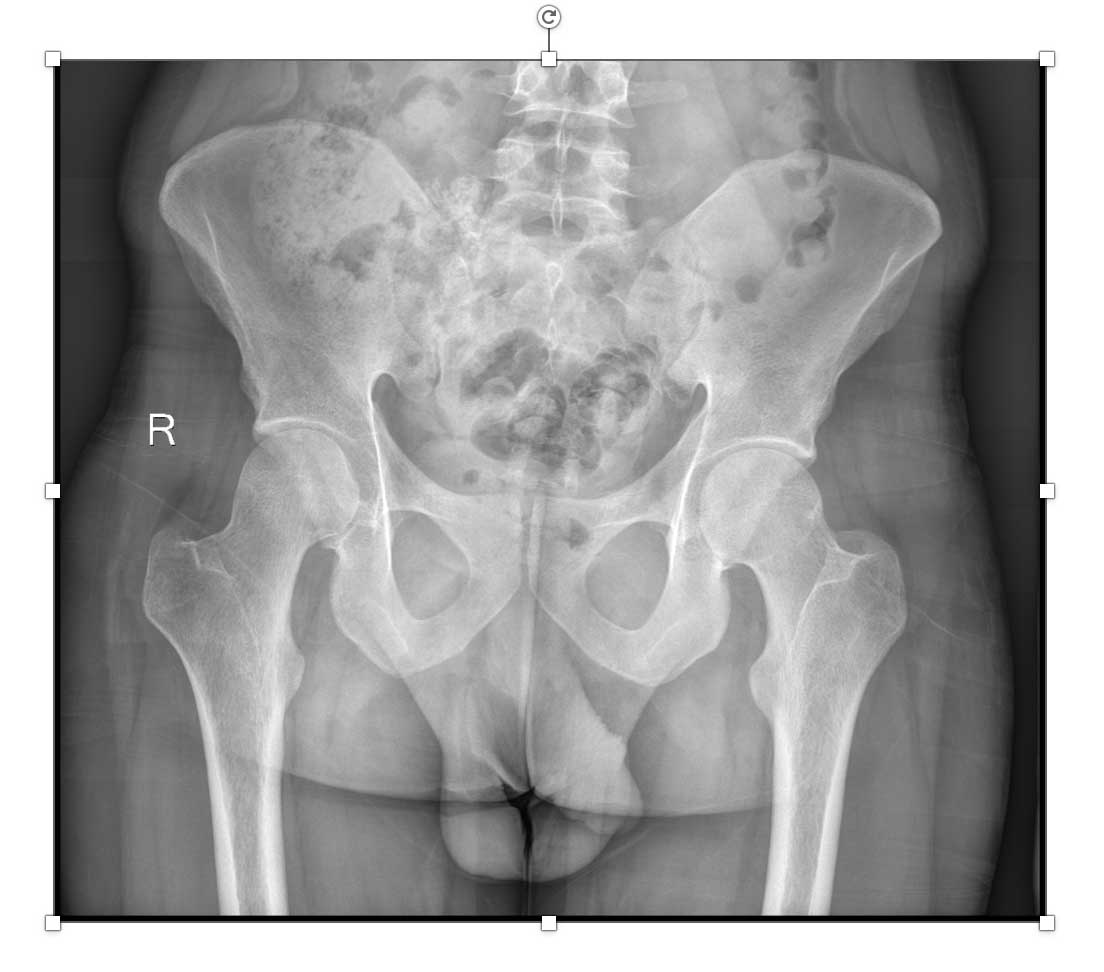

Ameliyat öncesi: Röntgende sağ sakroiliak bölgede düzensizlik ve ossifikasyon görülmekte.

Ameliyat öncesi: Tomografide sağ sakroiliak bölgede düzensizlik ve sklerozun eşlik ettiği tümör dokusu görülmekte.

Ameliyat öncesi:Tomografide sağ sakroiliak bölgede düzensizlik ve sklerozun eşlik ettiği tümör dokusu görülmekte.